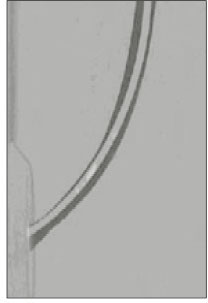

Ledge, Perforation

A total of three ledges and no perforation were created in the rotary instrumentation groups: one was in the ProFile .04 taper group and the other were in the HERO 642 group (Fig. 2. Direction of transportation 2). There were no significant differences between all three rotary groups(p>0.05). One perforation was created in the K-Flexofile group.

All of the canal at the end-point and the apex of curve were transported to outer aspects(Fig. 3).

Fig. 2

Composite image of the simulated root canal with ledge in the HERO 642 instrument.